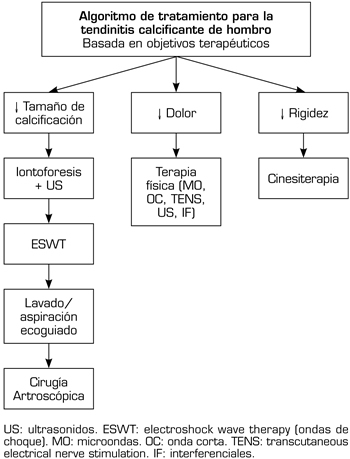

En nuestra serie, tras el tratamiento aplicado, de un 10,8 % que presentaron limitación funcional (n = 15), solo un 2,1 % permanecieron con la rigidez de hombro (n = 3), por lo que requirieron terapia manual posteriormente. Aunque no fue objetivo del presente estudio, debemos mencionar que tras 20 sesiones de terapia manual (en promedio), todos los pacientes recuperaron su movilidad (n = 3). Con esta consideración, recientemente hemos propuesto en un artículo de revisión, un algoritmo de tratamiento para la TC de hombro, en el cual proponemos que los pacientes con limitación funcional, deben realizar terapia manual (cinesiterapia) (32). Por otra parte, los pacientes con dolor pueden mejorar estos síntomas con diferentes técnicas rehabilitadoras (electroterapia, termoterapia, etc.). Mientras que, para la resolución definitiva de la calcificación, la iontoforesis con ácido acético constituye una modalidad rehabilitadora no invasiva de primera línea (32). Tratamientos de segunda línea incluyen a las ondas de choque. En caso de fracaso a las terapias previas, las medidas más invasivas incluyen al lavado aspiración ecoguiado y a la cirugía artroscópica (32) (Figura 6).

Fig. 6. Algoritmo de tratamiento para la tendinitis calcificante de hombro basada en objetivos terapéuticos (con autorización de Fernández-Cuadros y cols.) (32).